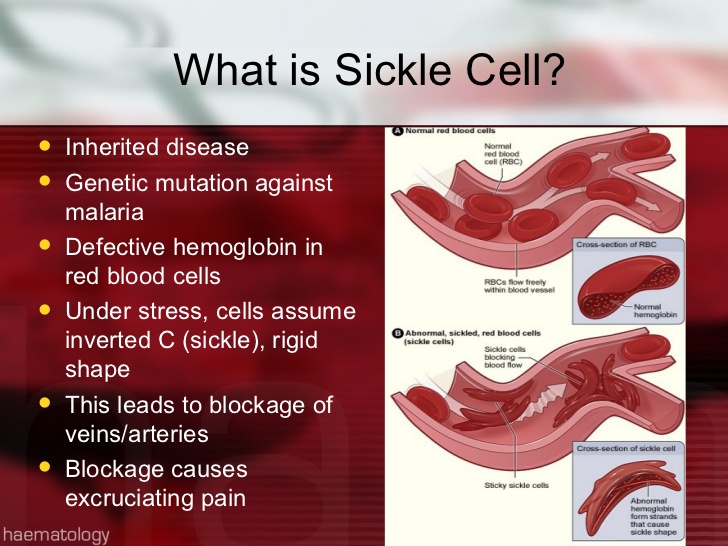

- Blood defects and diseases (e.g. leukemia, sickle cell anaemia etc.)

3. Hereditary- Sickle-cell anaemia, Colour blindness, etc

3. Hereditary- Sickle-cell anaemia, Colour blindness, etc